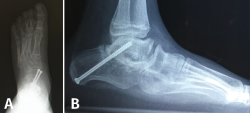

Astrágalo vertical congénito

El manejo es casi siempre quirúrgico y se basa en una liberación periastragalina extensa, corrección del equino del retropié, liberación de las fuerzas pronadoras y trasplante del TA sobre la cabeza del astrágalo. Dobbs(19) describió un tratamiento miniinvasivo basado en yesos seriados “antiponseti” reduciendo progresivamente la articulación TN llevando el pie en equino y aducción. Finalmente, se procede a una fijación temporal de la alineación TN con AK y corrección del equino mediante tenotomía de Aquiles (Figura 17). En caso de reducción insuficiente, se añade una liberación TN para permitir la reducción completa, que se mantiene temporalmente mediante AK retrógrada.

Figura 17. Astrágalo vertical congénito. A: diagnóstico radiológico; B: técnica Dobbs percutánea.